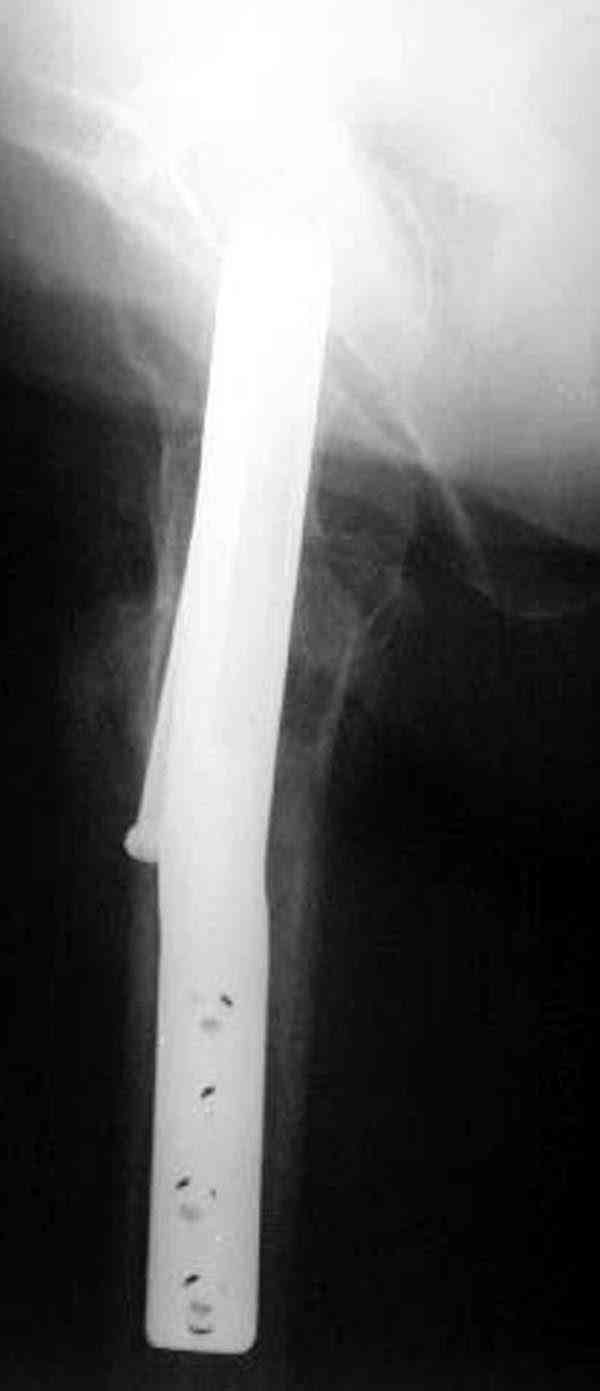

На Московской конференции в ноябре была продемонстрирована удивительная методика профилактического армирования шейки бедра у пациенток с остеопорозом и переломом контрлатеральной шейки в анамнезе.Странно, но дискуссии это сообщение не вызвало.Кто что думает об этом?

Спасибо, Антон. Я автор того сообщения по профилактическому армированию шейки бедренной кости, которое прозвучало на конференции, посвященной 50-летию создания АО. Мне тоже хотелось услышать вопросы по теме. Мы травматологи-ортопеды в первую очередь хирурги, а не терапевты. Почему в вопросе профилактики и лечения остеопороза мы ограничиваемся только консервативными методами лечения? Как можно практически научить больного не получать травмы, когда немало случаев возникновения переломов даже в постели. Первоначально идея армирования ШБК многих, при ком я озвучивал ее, шокировала, затем возникала дискуссия и большинство поддерживали эту идею. Мне бы очень хотелось развернуть дискуссию на странице этого сайта.

Уважаемый Антон! У меня было всего три клинических наблюдения, снимки были продемонстрированы на московской конференции. Количества этих снимков хватило для подачи заявки, а затем и получения патента на изобретение. В свое время РОСПАТЕНТ потребовал подтверждения методики клиническими наблюдениями. У одной из больных действительно произошла повторная травма, и произошел подвертельный перелом на стороне армированной шейки бедренной кости (см. снимки). Это подтвердило основную идею изобретения - была сохранена и головка, и армированная шейка бедренной кости. Но тут не обошлось безпроблем. Анестезиологи отказались давать наркоз, а провести остеосинтез под м/а пластиной и винтом DHS не согласилась больная. Дальнейшее лечение скелетным вытяжением. На контр. Рентгенограмме через 2 месяца признаки формирования костной мозоли. Повторных обращений двух других пациентов не было. Для более детальных исследований и выводов необходимо значительно большее количество клинических наблюдений. Такие исследования могли быть проведены в условиях клиник медуниверситета. Напомню, я работаю в травмотделении провинциальной городской больницы. Насчет экспертов страховых компаний, так пусть они выскажут свое мнение. Армирование кости - это плановые операции по желанию больного, какие здесь могут быть противоречия? На армирование все больные, к моему удивлению, согласились довольно легко и сразу, поэтому остеосинтез и армирование были проведены в течение одной операции. С уважением А.М.